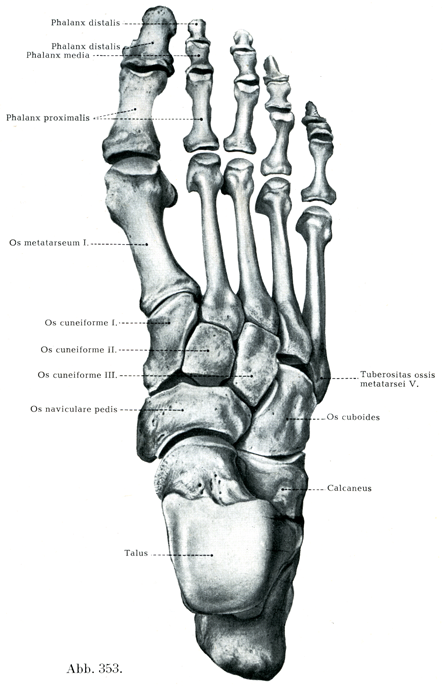

[図353]足の骨(右)足背面(6/7)

H. Virchow作製の標本(凍結骨格処理法によって,骨の相互の自然の間隔と正しい向きを保って組立てられている)